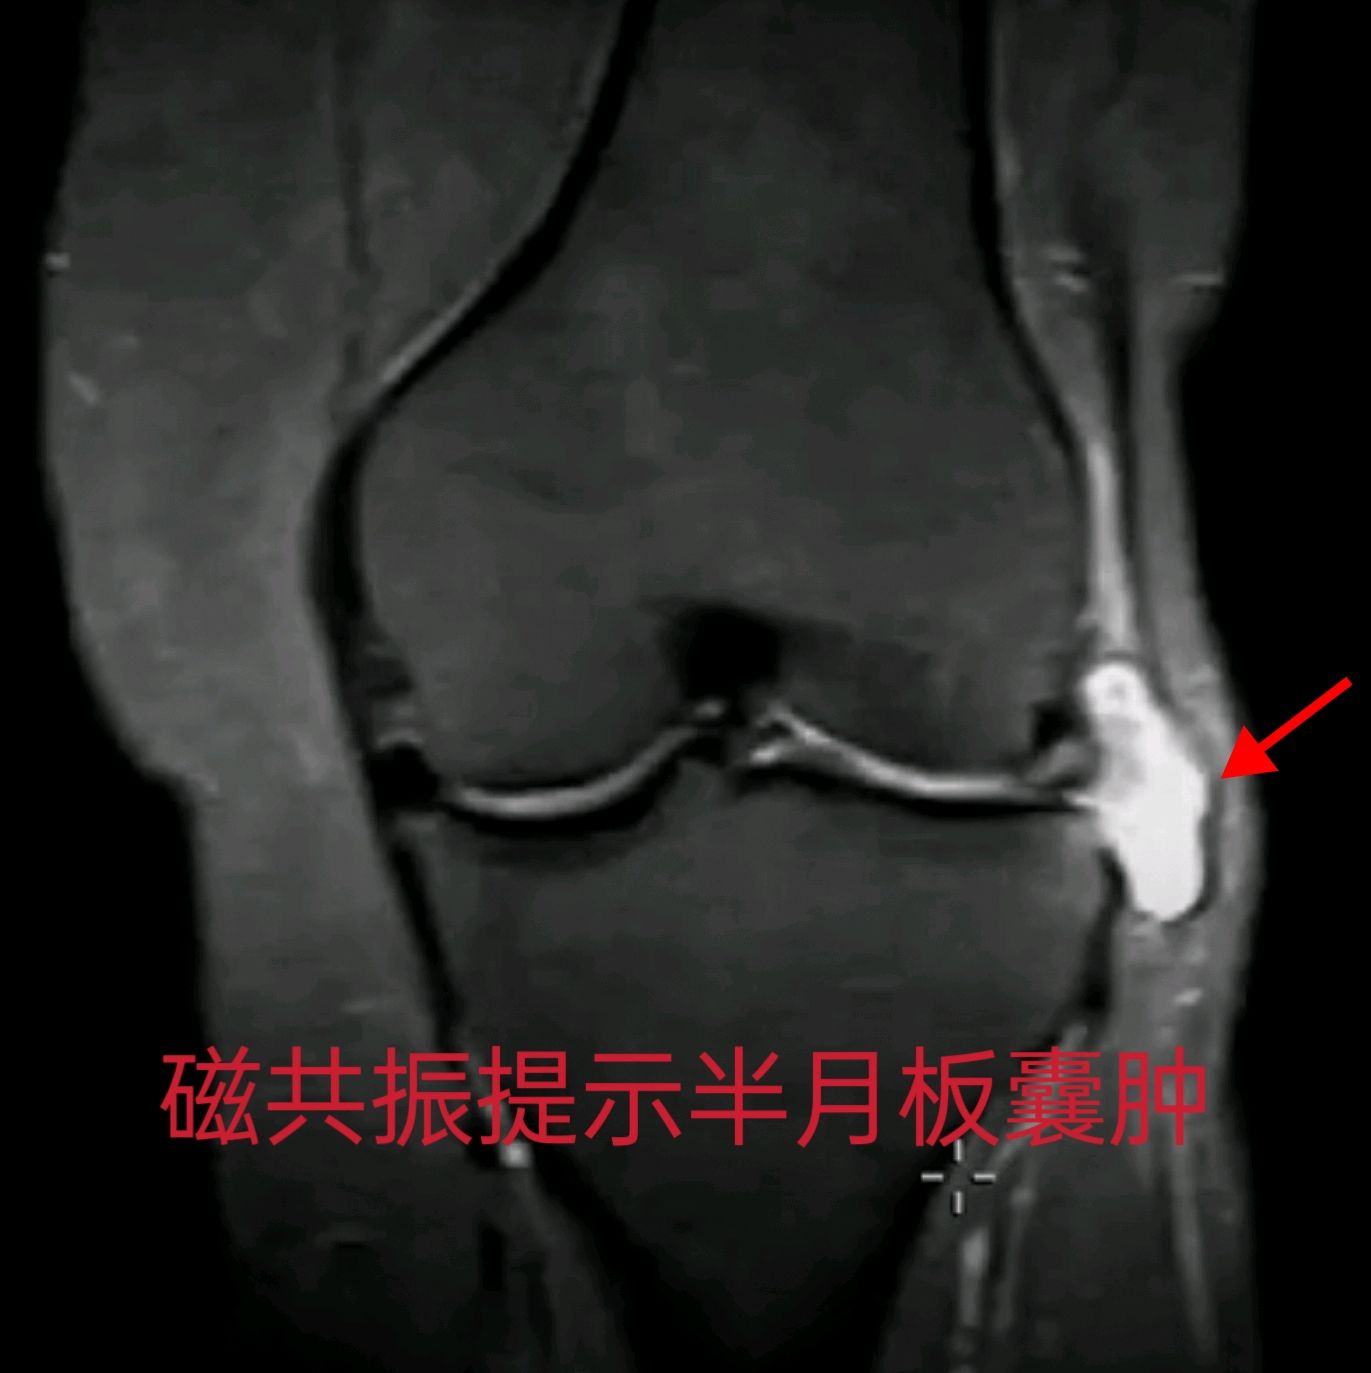

2. 完善检查:医生通常会建议进行膝关节核磁共振检查。MRI可以清晰地显示囊肿的大小、位置,以及半月板是否有撕裂、撕裂的类型和位置,这是制定治疗方案的最重要依据。